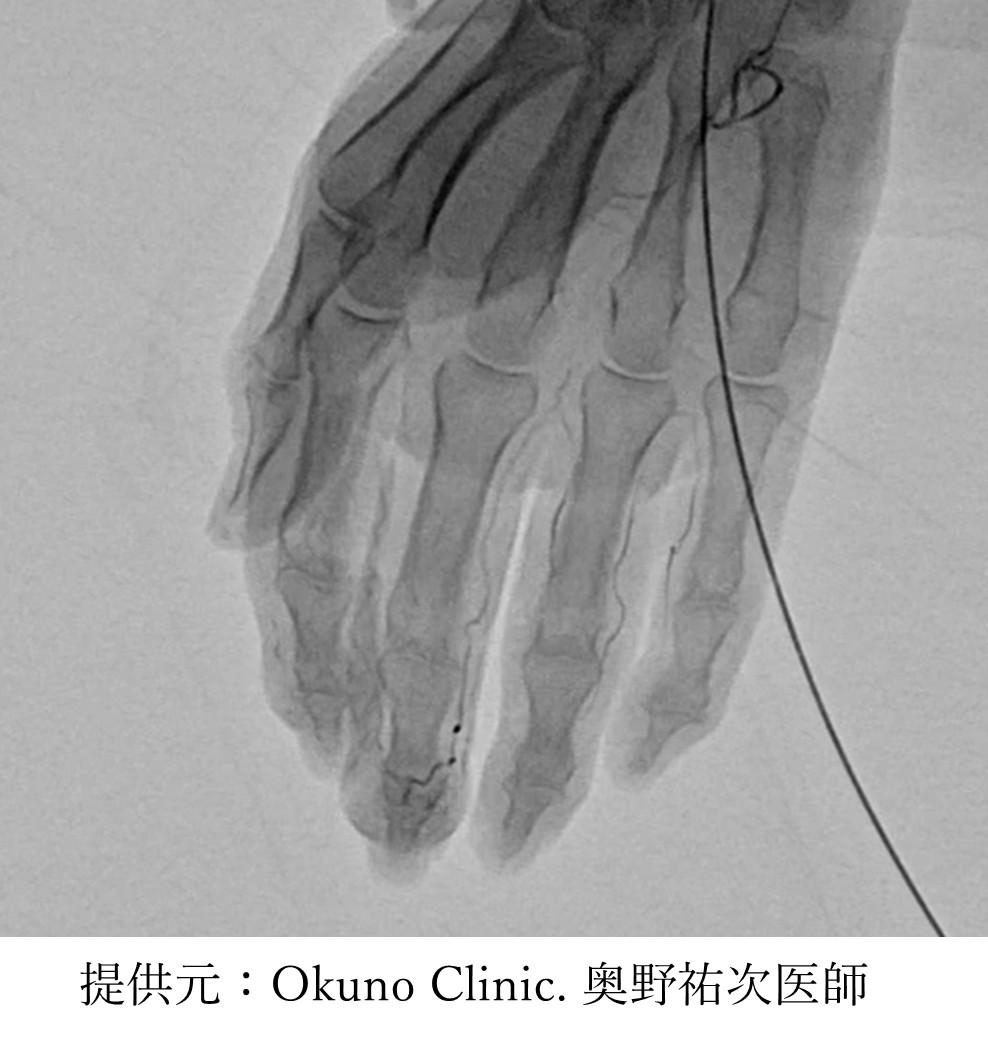

動注治療は、一般的な注射針もしくは点滴で使用する極めて細いチューブを用いて、手首ないしは足首の動脈から抗生物質でできた粒子(イミペネム・シラスタチン)を直接注入し痛みの原因部位にできてしまう異常な血管(モヤモヤ血管)を詰まらせることにより、炎症や痛みを軽減させる治療法です。動脈注射後、正常な血管は自身で拡張することにより詰まりを解消しますが、異常な血管は拡張することができないため詰まったままとなります。

この異常な増えた血管(モヤモヤ血管)を改善するための治療法が、2014年にオクノクリニック(https://okuno-y-clinic.com/)の奥野先生によって開発されました。

疾患により手首または足首に局所麻酔を行います。次に超音波検査を行いながら細い針を手首や足首の動脈に挿入して薬剤を注入します。エコーで血管内にあることを確認し薬液を入れていきます。注射された際に「びりびりする」「熱くなる」などの症状が生じることがありますが、数分で改善します。治療自体は5~10分程度で終了いたします。